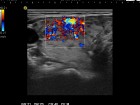

Follow-up examinations (rows from 1st to 8th):

Corresponding sonographic images (row)

2. Note the relation between volume, echogenicity, vascularization and hormone levels.